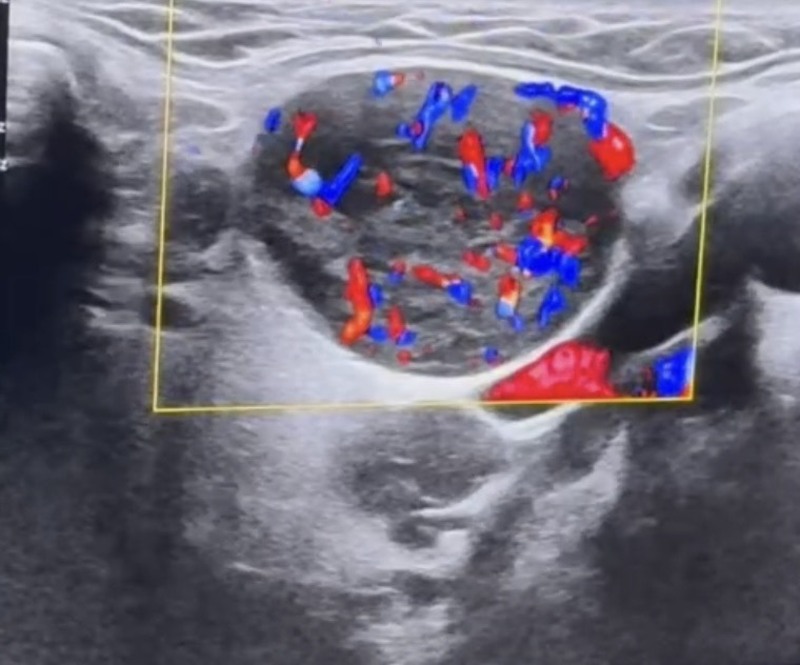

Đặc điểm siêu âm Doppler

- Mạch máu phân bố rốn hạch

- Trở kháng thấp

- Siêu âm:Vùng góc hàm bên trái ghi nhận vài cấu trúc hạch echo kém xen lẫn dải echo dày không đồng nhất, mất rốn, bờ đều kích thước từ 26-32mm, dạng bầu dục, mạch máu phân bố ngoại vi lẫn trung tâm.